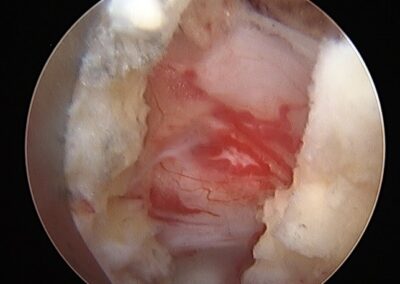

Figuras demonstrando os parafusos posteriores, o cage PLIF consolidado